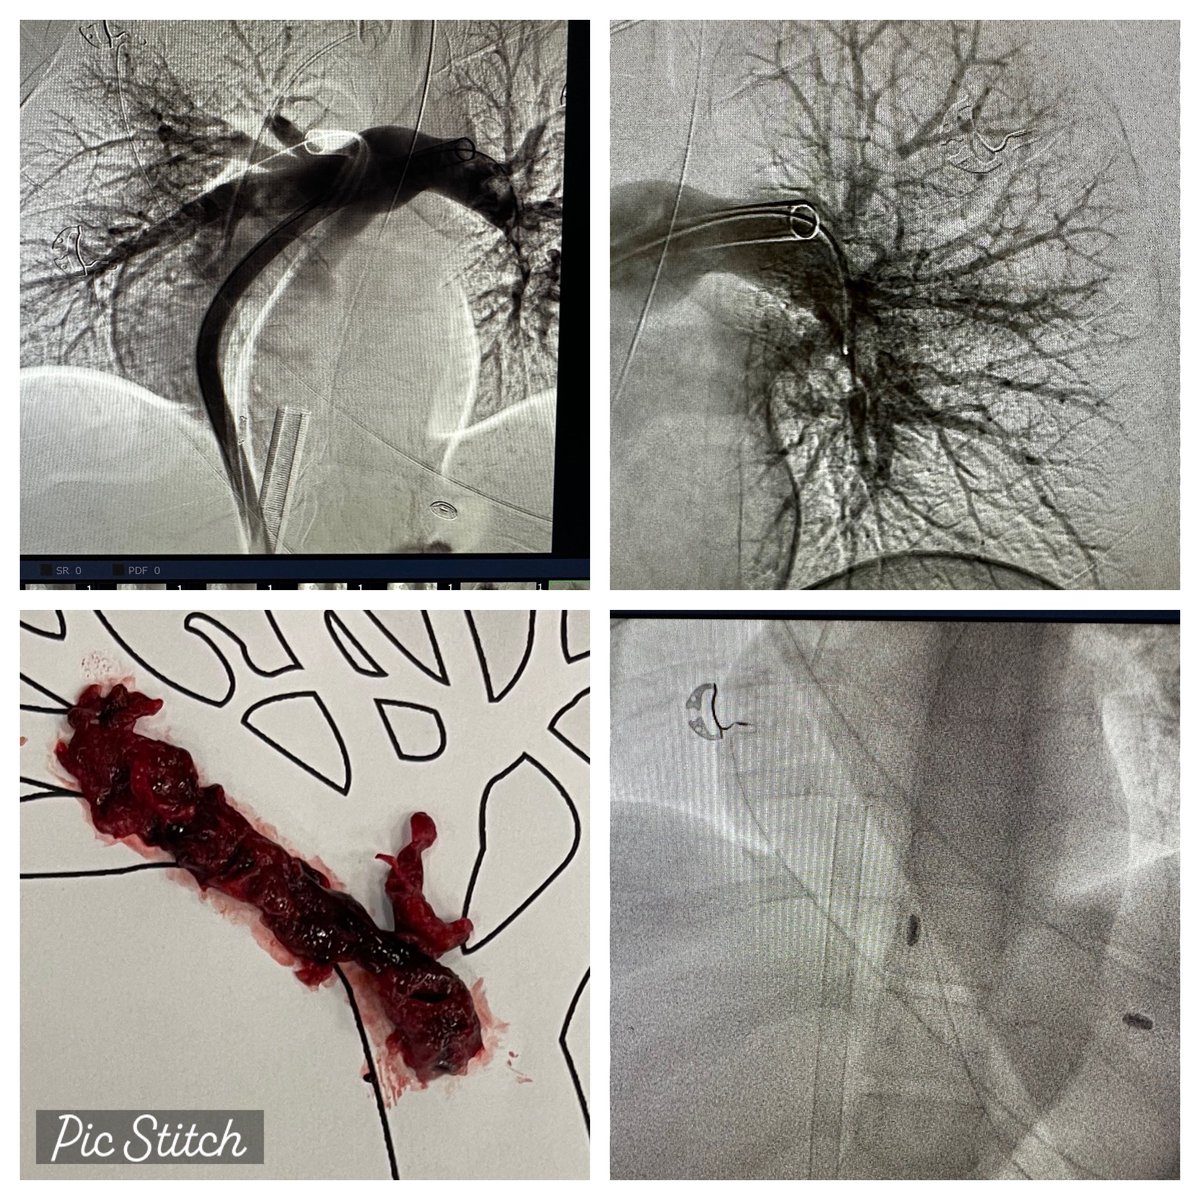

Interventional & Structural Cardiology Trained @MayoClinicCV @MUSChealth•Patient advocate. Lifelong learner.Opinions my own. #RadialFirst#TAVR#MitralClip#LAAO